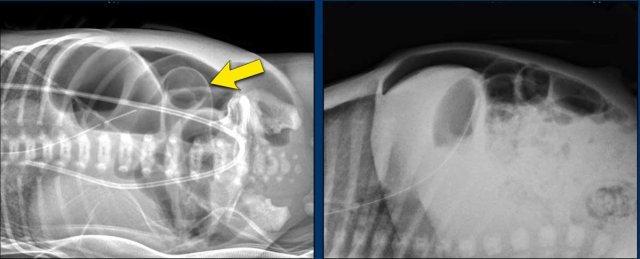

Free air

When necrosis progresses to perforation you can see free air or a pneumoperitoneum on the radiograph.

When you see free air on both sides of the bowel wall this is known as Rigler’s sign (arrow).

Football sign

On a supine radiograph free air may be seen under the diafragm outlining the falciforme ligament (figure).

This is known as the football sign, with the ligament representing the laces of an american football.

Of course, when you see any of these signs of free air, ultrasound is not needed anymore, since the NEC has progressed to a perforation and the surgeon should be contacted right away.

Gasless abdomen

Sometimes a perforation may present with a gasless abdomen.

There is ascites and peritonitis and the bowel is entirely collapsed.

This results in a white abdomen, which is not a good sign.

You may see some free air, as here in the upper abdomen, but sometimes the amounts of free air are too small to appreciate.

Ultrasound may help for further assessment.

Images

There is a nearly gasless or ‘white abdomen’ in a previously normal gas distribution.

There is only a small amount of free air present under the diaphragm.

For small amounts of free air ultrasound is more sensitive.